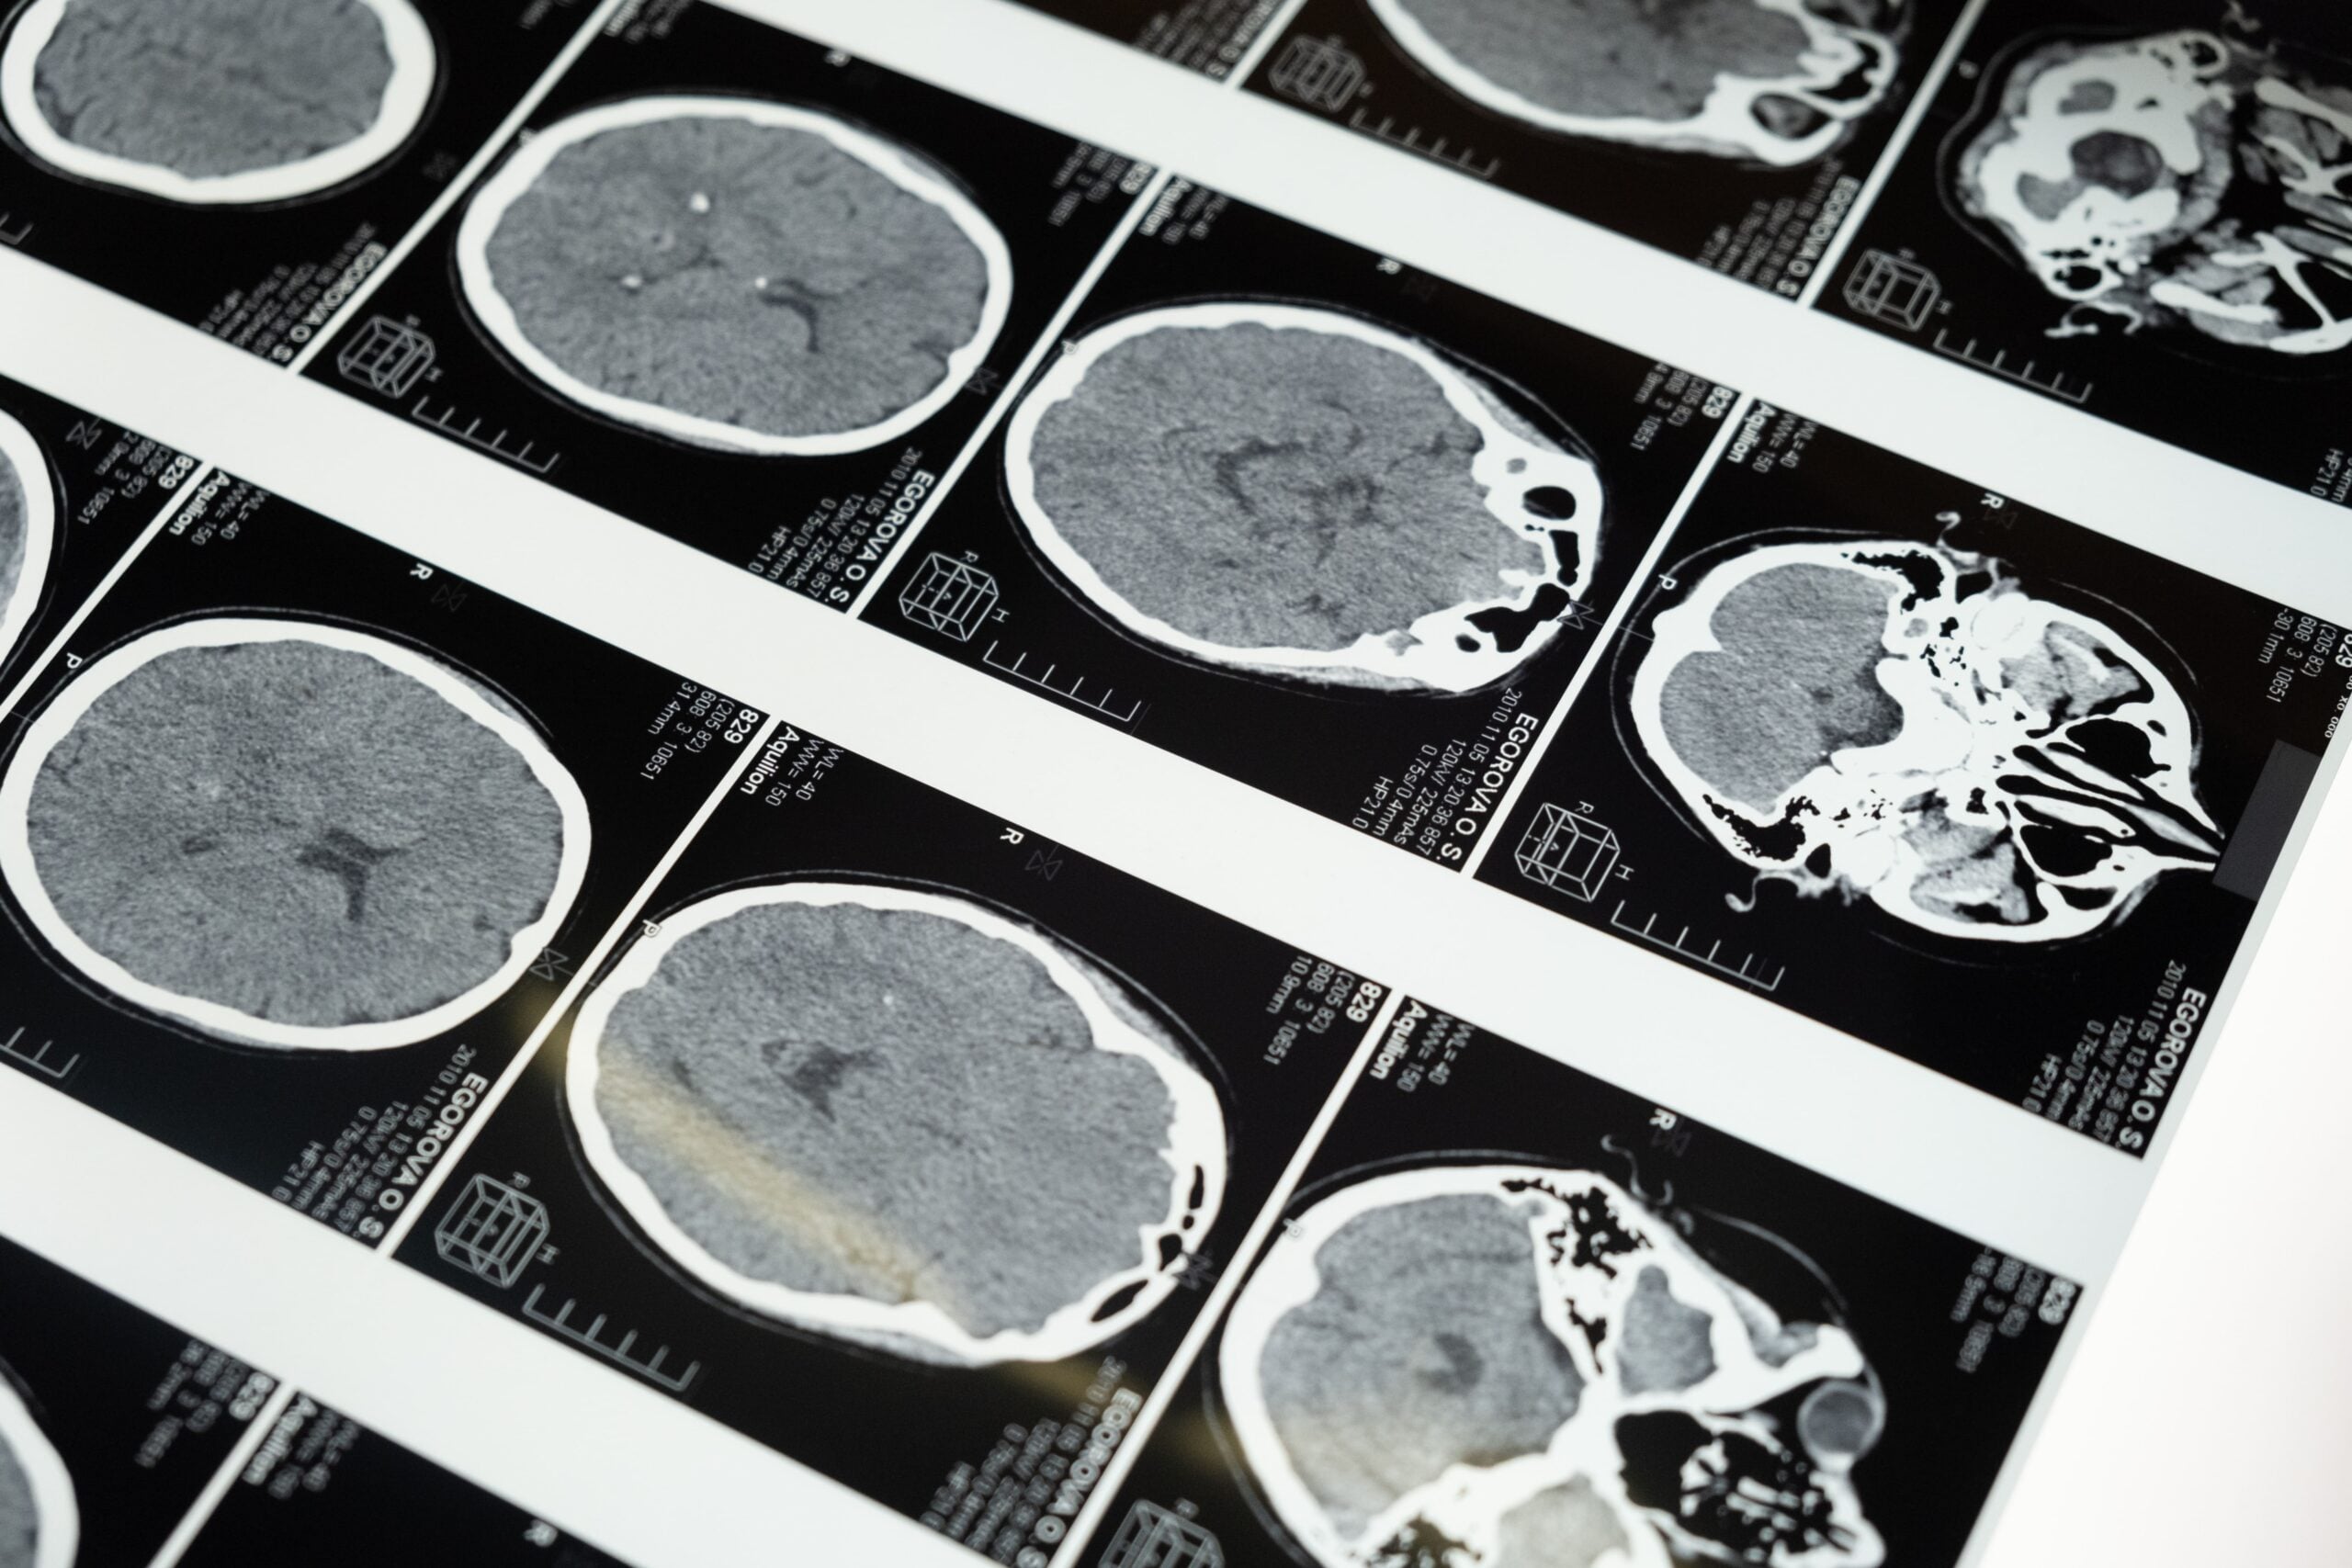

L’épilepsie est une maladie neurologique chronique qui se caractérise par des crises épileptiques récurrentes. Les crises sont causées par une activité électrique anormale et excessive dans le cerveau, ce qui peut provoquer des convulsions, des spasmes musculaires, une perte de conscience et d’autres symptômes.

Les crises peuvent être déclenchées par différents facteurs tels que le stress, la privation de sommeil, la consommation d’alcool ou de drogues, des blessures à la tête, des tumeurs cérébrales, des maladies infectieuses ou génétiques, ou des anomalies cérébrales congénitales.